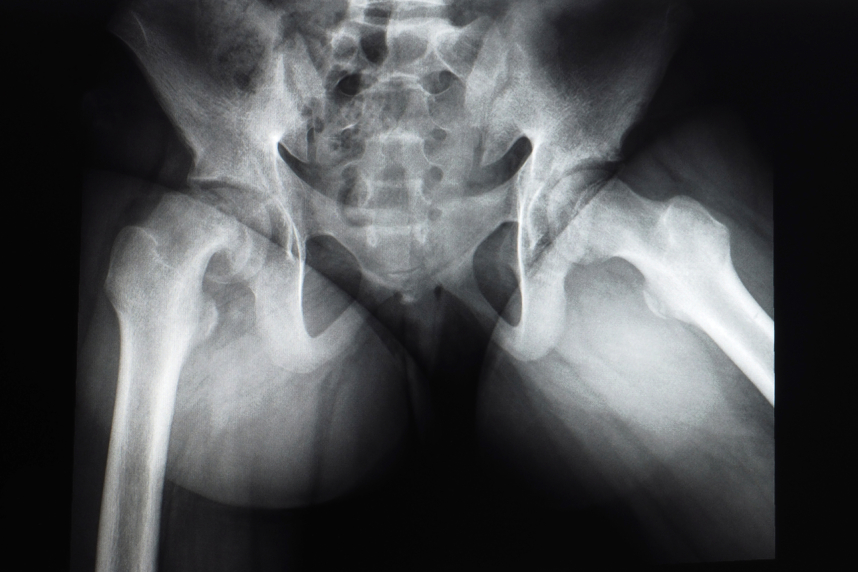

Articulatia soldului cunoscuta si sub denumirea de articulatie coxofemurala este alcatuita din 2 oase: coxal si femur. Coxalul are o cavitate unde patrunde femurul. In partea superioara, femurul prezinta cap femural, gat si col femural, acesta din urma nefiind orientat in directia corpului femural. Cand unghiul format intre gatul si colul femural este mai mare de 140 de grade, capul femural este deplasat in sus, iar deformarea se numeste coxa valga.

Unghiul cervico-diafizar format este mult mai mare decat ar trebui sa fie in mod normal, de peste 140 de grade (1), ceea ce reprezinta un risc crescut de luxatie de sold. Afectiunea poate fi observata la nou-nascuti, dar poate sa apara si la adulti.

Alaturi de examenul fizic complet, specialistul recomanda radiografia soldului sau chiar un CT.